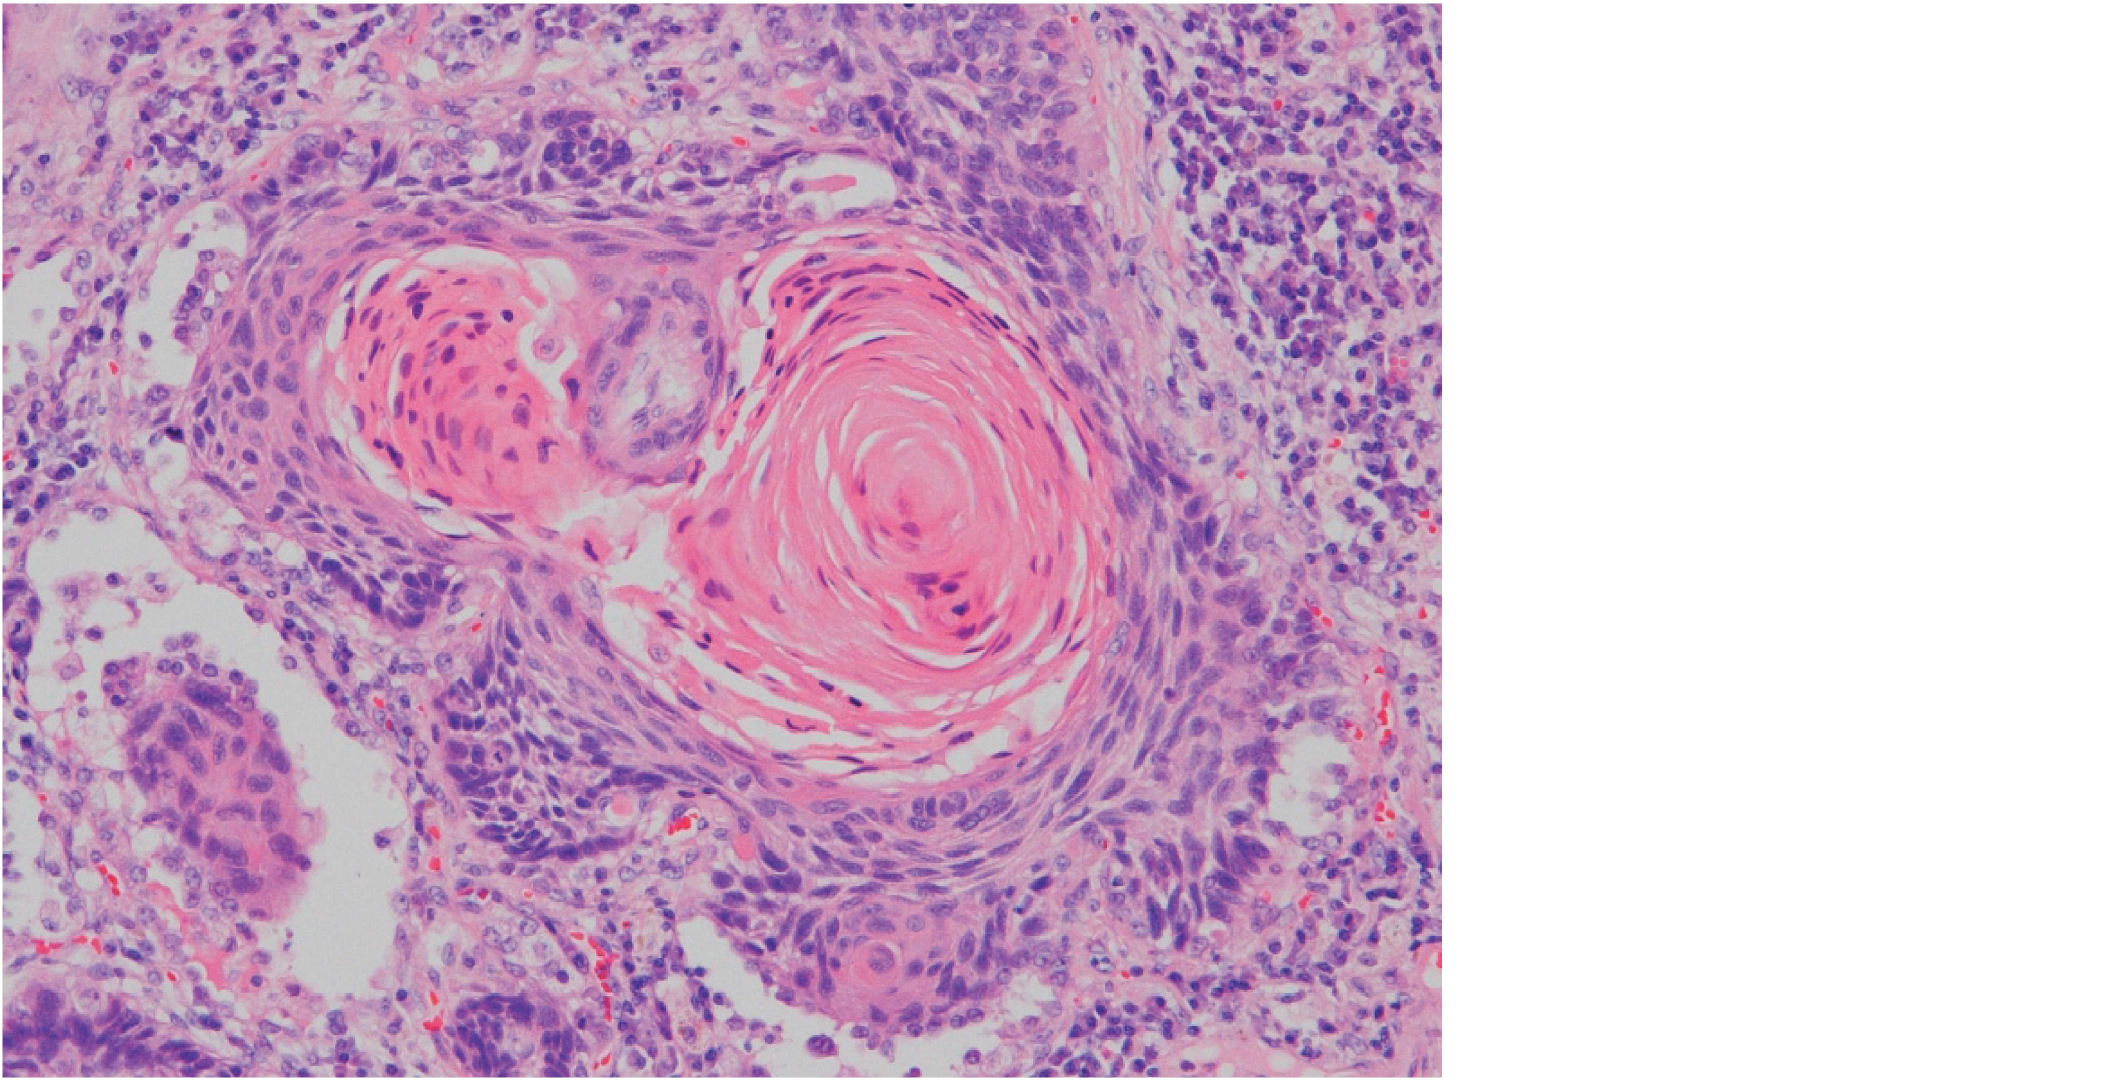

肺腫瘍のH-E染色標本を示す。

組織型はどれか。

1. 腺 癌

2. 小細胞癌

3. 軟骨肉腫

4. 扁平上皮癌

5. 悪性リンパ腫